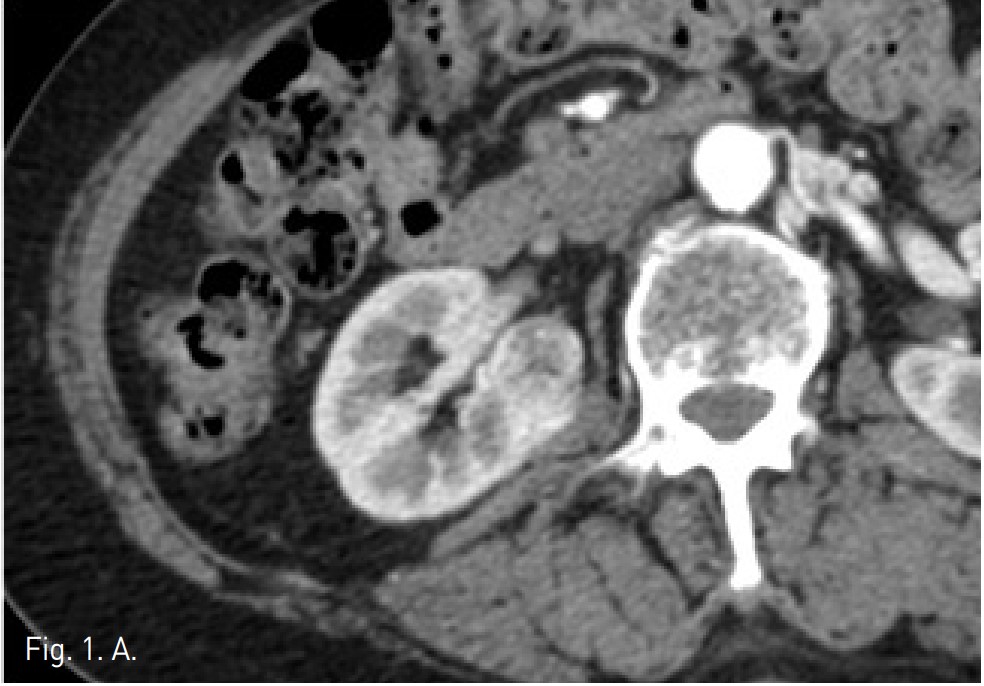

Fig. 1. B

Fig. 1. Kidney MDCT performed for a bulging contoured mass(biopsy proven RCC) in the interpolar portion of right kidney, which showed heterogeneously stong enhancement in the corticomedullary phase and (A) early washout in the nephrographic phase (B).

CT상 우측 신장 cortex 에 약 3.2cm 크기의 돌출하는 양상의 경계가 좋은 고형 종괴가 있음. 종괴는 신우에 인접해 있었으나 신주위 조직이나 신정맥으로의 침습 소견은 보이지 않았음 (Fig. 1A). 환자가 비수술적 치료를 원하여 고주파열치료를 위해 planning US를 시행하였으나 종양의 에코음영이 신실질과 유사하여 뚜렷이 구별되지 않고 (Fig. 2), 신우에 인접하고 있어 합병증의 위험성이 있고, 고주파 열치료만으로는 충분한 치료가 되지 않을 수 있어서, 동맥 색전술과 고주파열치료의 병합 치료를 하였음. 동맥 색전술과 고주파 열치료를 시행하고 9개월 이후 촬영한 CT에서 우측 신종양은 lipiodol이 compact하게 uptake되었으며 주변에 RF ablation zone이 관찰되고 viable portion이 없는 상태임(Fig. 5).